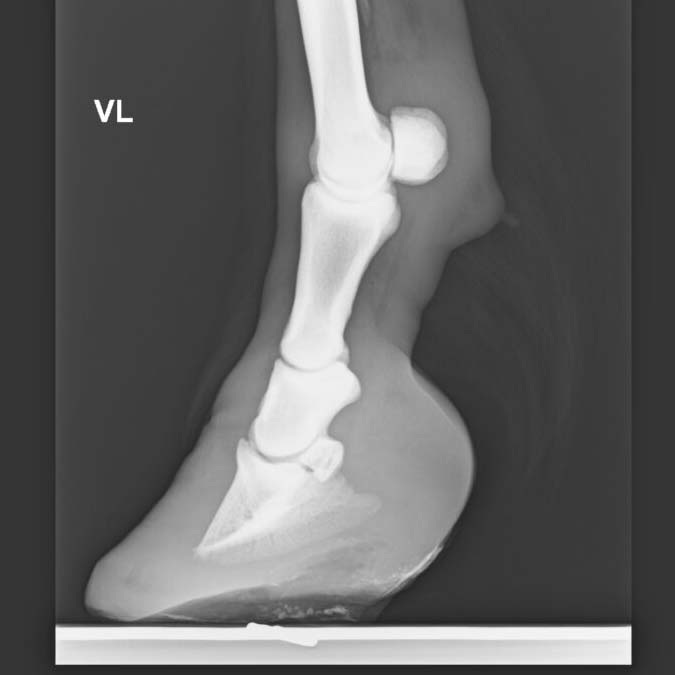

Hufeisen für Rehhufbeschlag

Bei dieser Krankheit, welche vorwiegend an den Vorderhufen, selten auch an den Hinterhufen auftreten kann, ist es wichtig, dass das Pferd möglichst schnell vom Tierarzt behandelt wird. Hier ist es wichtig, dass Tierarzt und Hufschmied zusammen den für das Pferd geeigneten Beschlag definieren. Heute wird anhand von Röntgenbildern entschieden, wie der Beschlag auszusehen hat. Dieser Entscheid hängt von der Rotation oder Absenkung des Hufbeins ab. Ein frühes Erkennen dieser Krankheit ist entscheidend. Zunehmend wird heute geklebt, um das gehen der Pferde zu unterstützen.